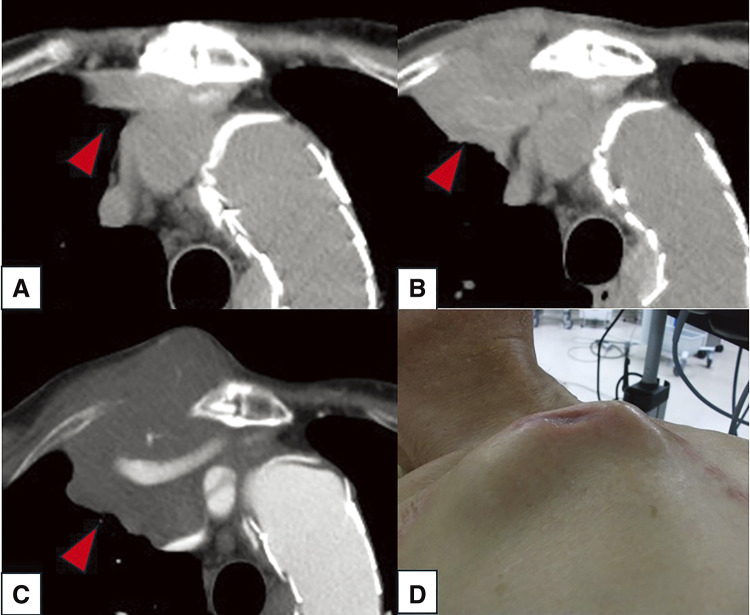

患者男,76岁,2年前行胸腔血管内主动脉修复术后逆行A型主动脉夹层右腋窝动脉搭桥及弓置换术,主诉右侧锁骨下区肿胀疼痛。计算机断层扫描怀疑旁路移植周围有脓肿;然而,文化是消极的。病理检查显示弥漫性大b细胞淋巴瘤(DLBCL)。由于患者病情不适合化疗,3个月后去世。起源于移植物周围的DLBCL极为罕见,但对鉴别诊断至关重要。

A 76-year-old male patient, who had undergone right axillary artery bypass and arch replacement surgery for retrograde type A aortic dissection after thoracic endovascular aortic repair 2 years ago, was referred to our department with complaints of swelling and pain in the right subclavian region. A computed tomography scan suspected an abscess around the bypass graft; however, the culture was negative. Pathological examination indicated a diffuse large B-cell lymphoma (DLBCL) diagnosis. Chemotherapy was not indicated due to the patient's condition, and he passed away after 3 months. DLBCL originating around a graft is extremely rare but crucial for differential diagnosis.